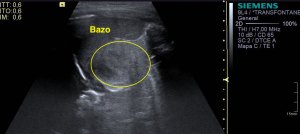

Como el quiste era tan grande tuve que usar «Panoramic View» para poder hacer una medida y estudiar hasta donde llegaba el quiste.